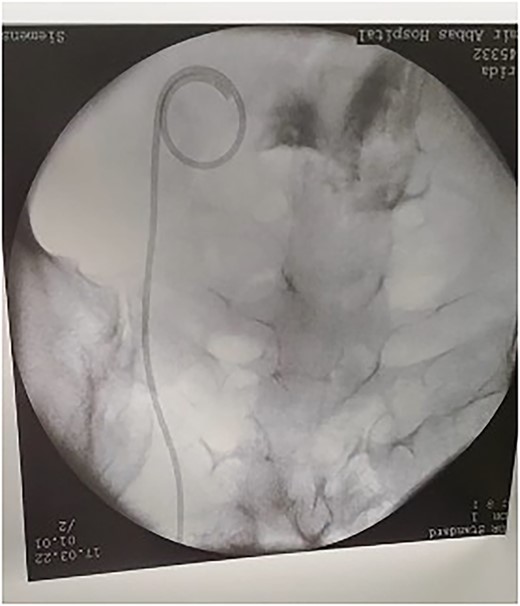

The patient tolerated the procedure very well and was transferred to the recovery room in stable condition. We did inform the patient that there is a small likelihood of developing a fistula within 2 weeks post-operatively. The patient did well in the post-operative period, recovered and was discharged to home in a stable condition. Unfortunately, on day 8, post-operatively, she started to have a leakage of urine per vagina. She was admitted for investigation, a CT Urogram was done with delayed images that confirmed the diagnosis of ureterovaginal fistula. The urologist was involved and consulted at this point; the plan was to take the patient for cystoscopy with retrograde ureteroscopy. Ureteroscopy wth retrograde fluoroscopy showed evidence of a ureterovaginal fistula (Figs 4 and 5) in which a DJ stent was inserted successfully (Fig. 6). The patient was explained about the post-operative course and plan. We decided to keep the stent for 12 weeks and then re-assess. The patient was covered by prophylaxis low-dose nitrofurantoin single daily dose of 100 mg. Fortunately, the leakage decreased gradually until it stopped. The patient was taken to the operating room to re-assess the fistula by cystoscopy and retrograde fluoroscopy. Retrograde fluoroscopy confirmed that the fistula healed. The stent was removed, and the patient was discharged to home in a stable condition.